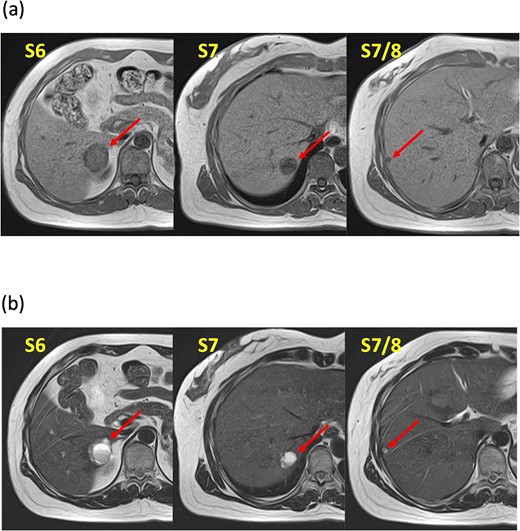

A 52-year-old woman was admitted to our hospital for the evaluation and treatment of multiple cystic liver tumors. Two years earlier, dynamic computed tomography (CT) had detected multiple cystic tumors in segments 6 (S6) and 7 (S7), which were subsequently monitored (Fig. 1a). The patient showed no symptoms; laboratory tests for tumor markers such as α-fetoprotein, protein induced by vitamin K absence or antagonist-II, carcinoembryonic antigen, and carbohydrate antigen 19–9 were within normal ranges. Dynamic CT identified two low-density tumors with peripheral enhancement in the portal phase, featuring cyst-like internal septa (Fig. 1b), which showed slow enlargement over 2 years. Magnetic resonance imaging (MRI) using gadoxetic acid (gadolinium-ethoxybenzyl-diethylenetriamine pentaacetic acid; EOB Primovist®) revealed that tumors appeared as low intensity signals on T1-weighted imaging and high intensity signals on T2-weighted imaging and diffusion-weighted imaging. Additionally, a 7-mm lesion was observed at the S7/8 boundary (Fig. 2a and b). Positron emission tomography-CT (PET-CT) showed abnormal uptake in S6 and S7 tumors but not in the S7/8 lesion (Fig. 3). CT during hepatic arteriography (CTHA) demonstrated well-contrasted tumors at the periphery, with no contrast enhancement in the center (Fig. 4a). Moreover, CTHA detected a new tumor in S8, displaying clear and uniform contrast but not visible with other imaging modalities (Fig. 4b).

Computed tomography during hepatic arteriography findings. (a) Known tumors in S6, S7, and S7/8 exhibit peripheral contrast enhancement but lack contrast in their centers. (b) The new tumor in S8 displays a distinct, uniform contrast effect.